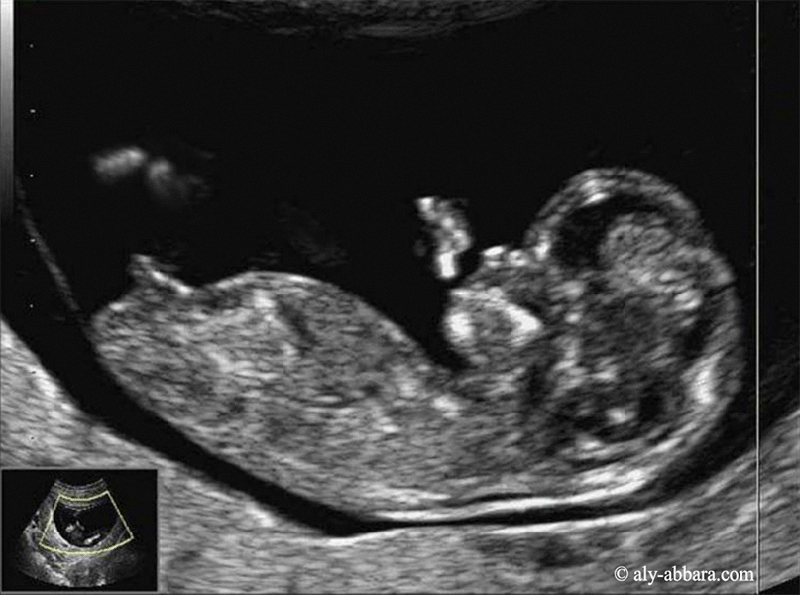

| Les conditions nécessaires pour obtenir une mesure valable de la longueur crânio-caudale afin de déterminer la date du début de grossesse. |

- Critères de qualité de la mesure de LCC sont :

- il est fortement recommander de déterminer la date du début de la grossesse par le recours à la mesure échographique de la longueur crânio-caudale fœtale (LCC) entre (11+0SA et 13+6SA) ce qui correspond à une mesure de la (LCC) située entre 45 et 84 mm.

- La coupe fœtale doit occuper > 50 % du champ de l'image.

- La coupe fœtale est sagittale.

- Quelques signes pour se rapprocher le plus de la coupe sagittale idéale :

- bourgeon sexuel visible ;

- cordon ombilical visible à sa base ;

- os malaire non visible et ;

- os propre du nez visible ;

- diencéphale visible et il est préférable que les ventricules cérébraux latéraux ne soient pas visibles.

- La position fœtale est neutre (ni en hyper-flexion ni en hyper-déflexion).

- L'extrémité céphalique fœtale est dégagée.

- L'extrémité caudale fœtale est dégagée.

- Les

curseurs sont biens placés.